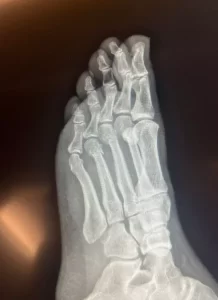

CHP Genel Başkanı Özgür Özel’in “Herkes inceleyebilir” dediği filmleri inceleyen Ortopedist Prof.Dr. Tarık Yazar, değerlendirmelerde bulundu.

Prof. Yazar, Özgür Özel’e ait elimizdeki röntgen filmlerini inceleyerek şunları söyledi:

“Sayın Özgür Özel’in röntgen filmlerini incelediğimizde parmak kemiklerindeki kırıkları gördüm. Açık bir yara olmaması bir şanstır. Yani, dışarıya kan akmamış. Röntgende yara olup olmadığı her zaman görülmez. Ancak, Özgür Bey’in röntgenini incelediğimizde yine de şanslı olduğunu gördüm. Biz buna ‘şanslı kırık’ deriz. Aslında tam kırık da diyemeyiz. Ayrılmamış, kemiğin özelliği bozulmamış. İyileşme yeteneğinin fazla olduğu bir bölgede kırık var. Şanslı tarafı kanlanmanın kuvvetli olduğu bir bölgede kırık gördüm. Bilgisayarlı tomografiyle takibi uygun olur. Tedaviye doğru başlanmış. Mutlaka iyileşecektir. Kullandığı ayak desteği gayet doğru bir seçim. Üç aya kalmaz tam iyileşme gerçekleşir. Lütfen bir daha düşmesin.”